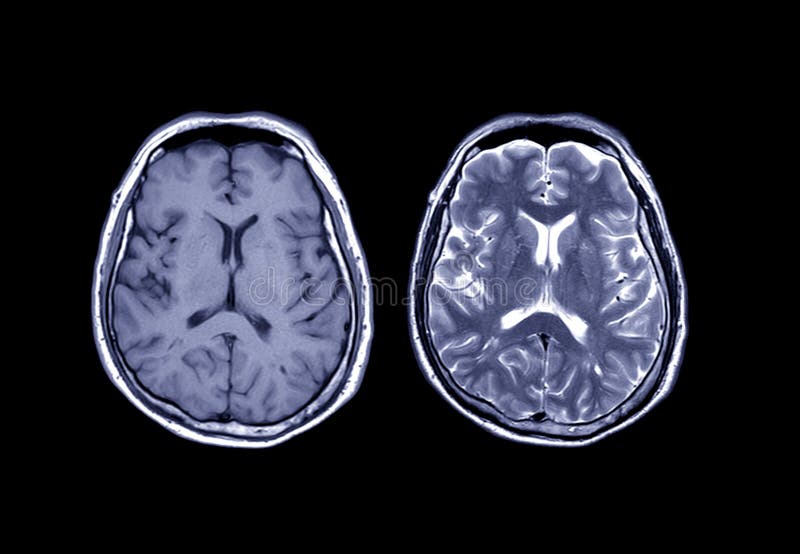

ガドリニウム:MRIで造影といえばこれ。 超磁性体酸化鉄粒子 SPIO:肝網内系をターゲットとした造影剤である。SPIOはKupffer細胞に貪食されリソソームにクラスター化される家庭でT2*緩和時間およびT2緩和. くはない3).mriでは,鉄沈着による局所の磁場 の不均一により,t1,t2及びt2*緩和時間が 短縮する特性を利用して肝内鉄沈着の評価が可 能である.特にt2及びt2*とそれらの逆数であ るr2及びr2*は鉄濃度と比例して変化するた 一口メモ 図3 肝生検組織所見. 頭部mriの見方です。 基本は 水 = 脳脊髄液 を見ます。 脳脊髄液は脳室や脳の表面にあります。 t1なら黒 t2なら白です。 話が難しいのは mriに….

〈medix vol.50〉 41 1.はじめに mri検査において基本シーケンスはt2強調画像とt1強調 画像である。かかりつけ医の医療の場において、診断能向上の. 頭部MRI の基礎 -頭部MRI で撮られる各画像について- 友愛会南部病院 仁井田 明 要旨 現在、日常的に撮影されている頭部MRI(Magnetic resonance imaging :磁気 共鳴画像法)画像にはT1 強調像(T1WI)、T2 強調像(T2WI)、プロトン密度強 調像(PDWI)あるいはFLAIR(FLuid-Attenuated Inversion Recovery)像. 3T MRIの組織コントラスト能の特徴 T1強調画像 de Bazelaireらの研究 1) によると,腹部領域における3Tと1.5Tの緩和時間の違いは,肝臓,脾臓,膵臓では,3TでT1値が著明に延長するのに対し,筋肉では緩和時間に差がなく,結果的に,3Tでは肝臓,膵臓,筋肉でのT1値の差が少なくなる。.